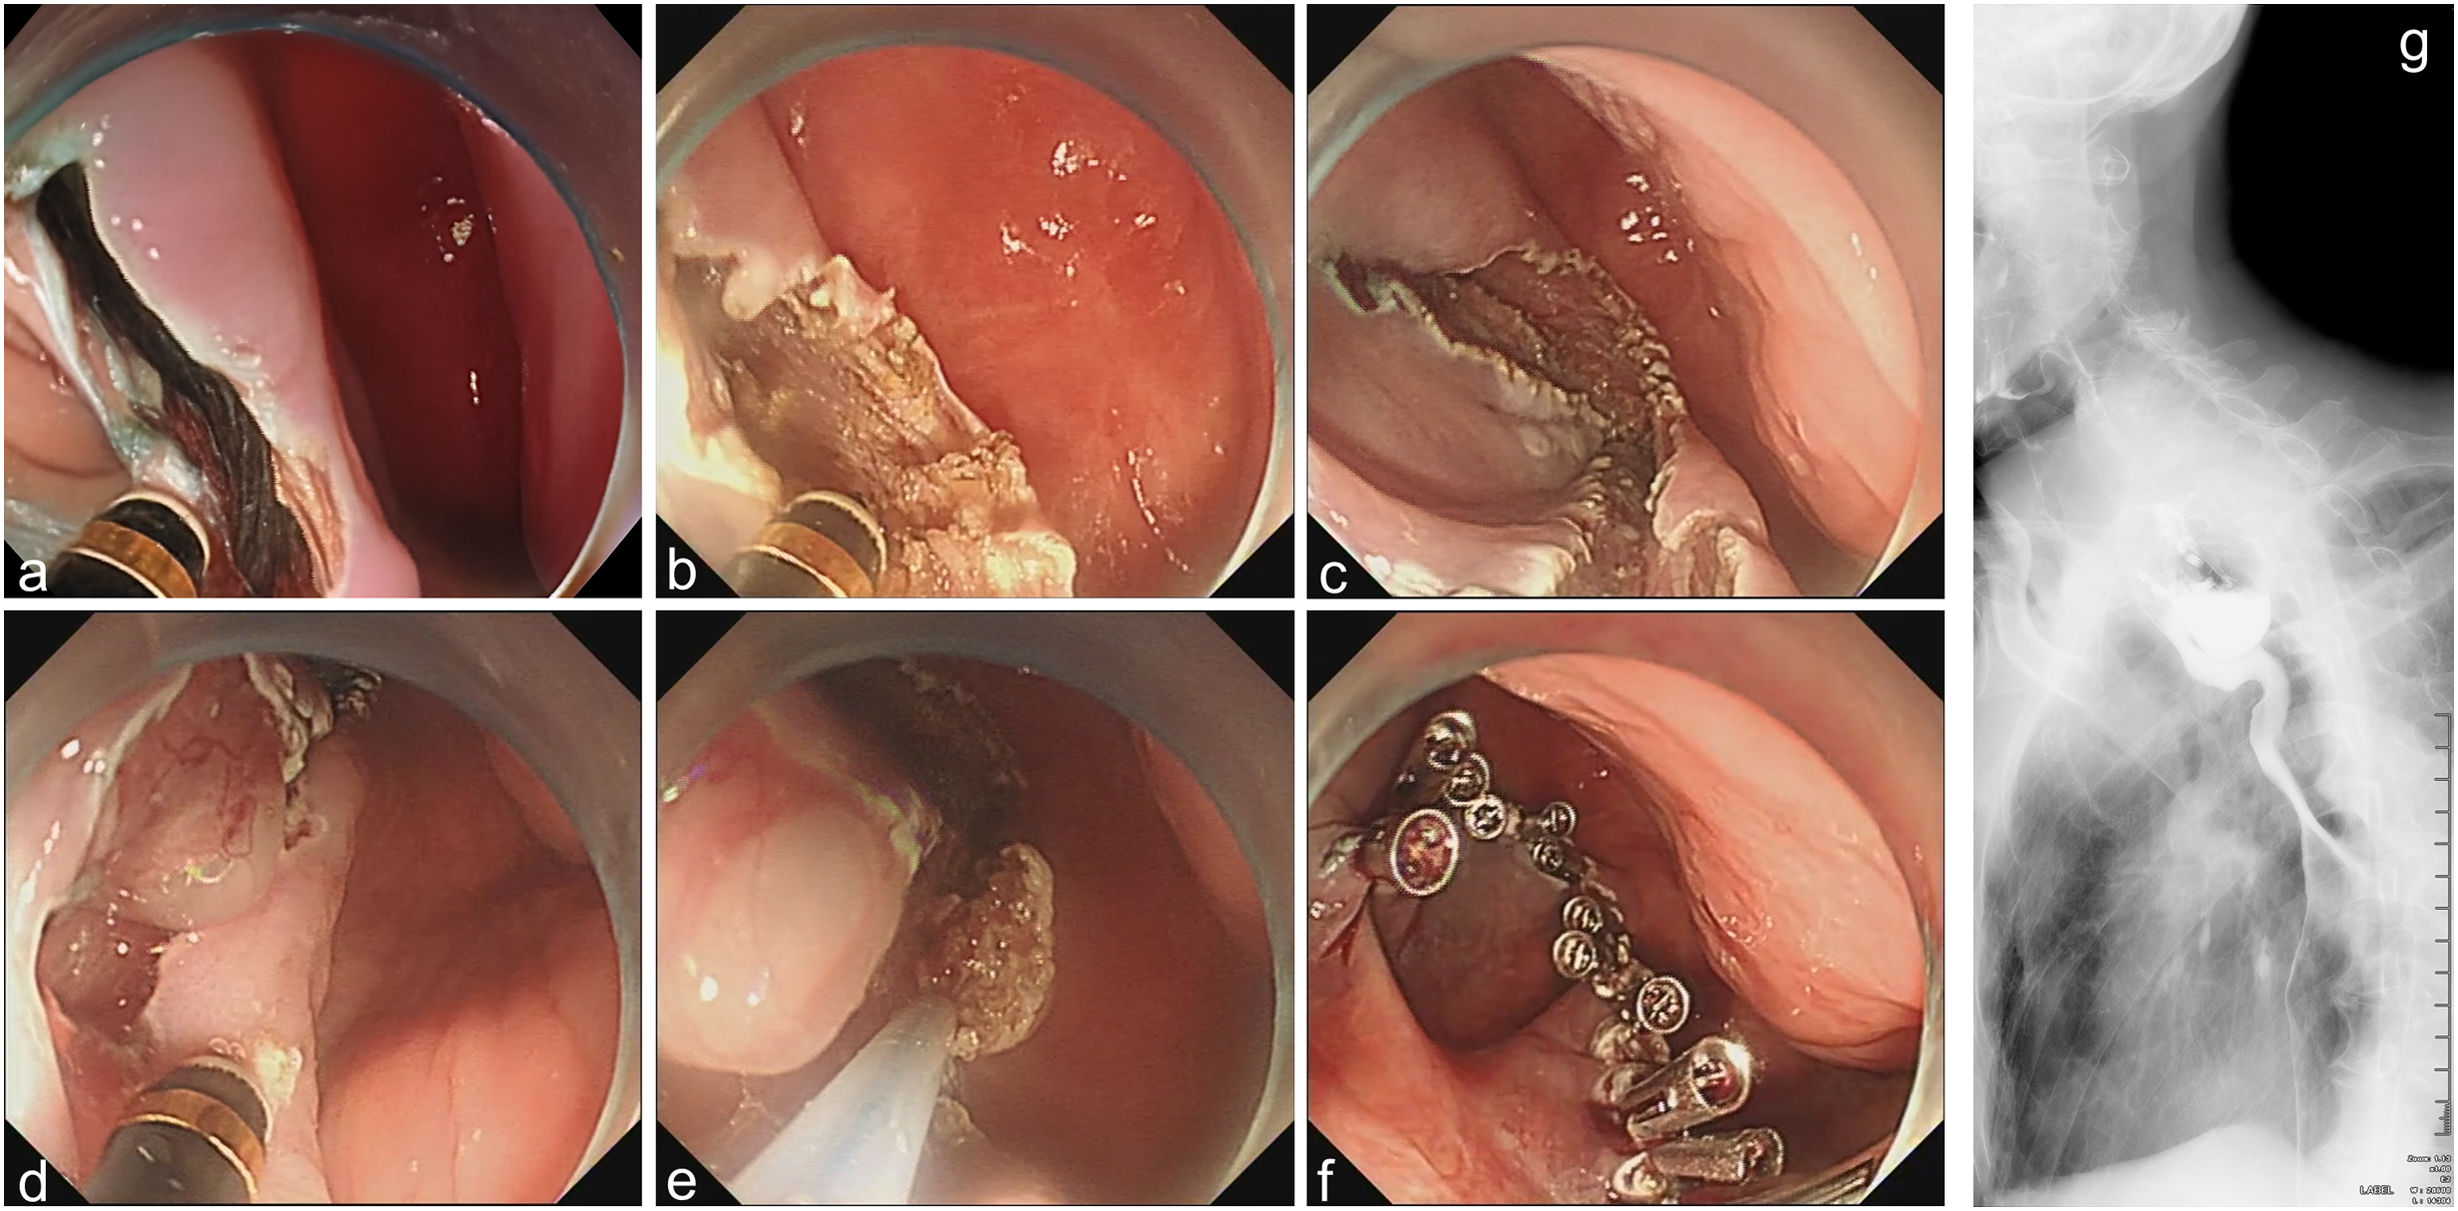

To address this, transection of the residual mucosal flap was extended to the diverticular base using a Disposable High-Frequency Incision Knife (MK-T-2-195. Nanjing Micro-Tech Medical) (Fig. 2a and b). Mobile septum resection yielded irregular margins (Fig. 2c). Small protruding flaps underwent cold snare polypectomy (Captivator™ II, Boston Scientific). For larger flaps (>10mm), initial incision was performed using incision knife (MK-T-2-195. Nanjing Micro-Tech Medical), followed by snare resection (Captivator™ II) (Fig. 2d and e). The mucosal defect was closed with six through-the-scope clips (Resolution™ Clip, Boston Scientific) (Fig. 2f). Postoperative esophagram on day 7 confirmed unimpeded barium passage (Fig. 2g). At the 3-month follow-up, the patient demonstrated complete resolution of dysphagia with absence of reflux symptoms, accompanied by a 2.3kg body weight gain.

Modified Z-POEM. (a) Bilateral mucosotomy; (b) full-thickness septotomy extending to the diverticular base; (c) irregular mucosal margin with >1mm serration; (d) precise incision of protruded septal remnants using incision knife; (e) resection with snare; (f) complete mucosal closure using clips; (g) postoperative day-7 esophagram confirming diverticular resolution and absence of contrast extravasation.